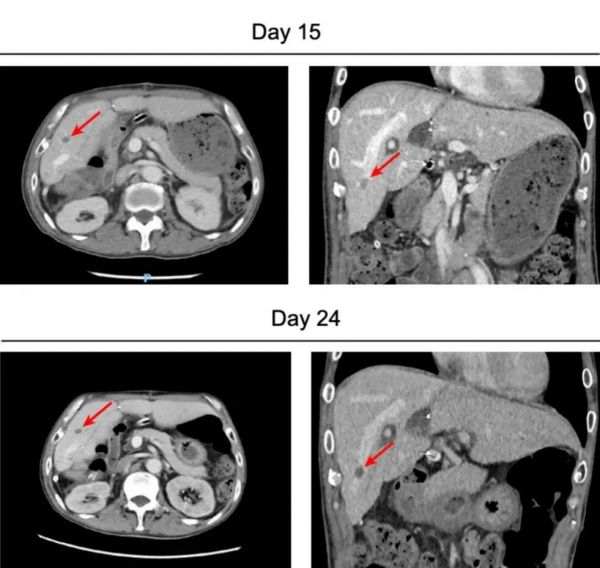

术后早期,患者即出现纤维蛋白/纤维蛋白原降解产物(FDP)和 D-二聚体水平的持续升高,虽然持续使用依诺肝素进行抗凝治疗以预防血栓,但 CT 显示,移植后的猪肝内肝静脉末端有一小结节性血栓。

图源:参考资料 1